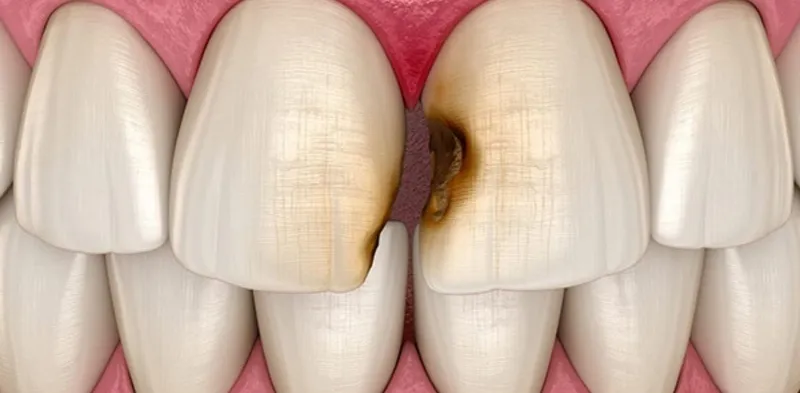

Sâu kẽ răng là tình trạng kẽ hở giữa hai răng liền kề bị vi khuẩn tấn công gây tổn thương cấu trúc răng. Vi khuẩn trong mảng bám và thức ăn thừa tích tụ tại các kẽ răng phát triển mạnh, ăn mòn lớp men răng và tạo nên các vệt đen mất thẩm mỹ.

Khi bị sâu kẽ răng, vi khuẩn sẽ dần ăn mòn cấu trúc răng, từ lớp men bên ngoài đến lớp ngà bên trong, có thể lan đến tủy răng nếu không được điều trị kịp thời. Tình trạng này không chỉ ảnh hưởng đến thẩm mỹ mà còn gây ra các cơn đau nhức và có thể dẫn đến mất răng.

- Xuất hiện vết đen ở mặt tiếp xúc giữa các răng: Đa số các trường hợp bị sâu kẽ răng đều có các vết đen xuất hiện tại vị trí kẽ giữa hai răng liền kề. Những vết đen này có thể phát triển dần và tạo nên khoảng trống giữa hai răng, ảnh hưởng đến thẩm mỹ.

- Sâu men răng: Đây là giai đoạn đầu và nhẹ nhất khi bị sâu kẽ răng. Dấu hiệu nhận biết là xuất hiện các vệt vàng hoặc nâu nhạt tại kẽ răng. Ở giai đoạn này, nếu phát hiện và điều trị kịp thời, răng có thể được phục hồi hoàn toàn.

- Sâu ngà nông: Giai đoạn tiếp theo của sâu kẽ răng khi vi khuẩn đã ăn mòn qua lớp men và tạo ra các lỗ nhỏ li ti trên răng. Ở giai đoạn này, người bệnh thường cảm thấy khó chịu khi ăn uống đồ nóng, lạnh hoặc ngọt.

- Sâu ngà sâu: Đây là giai đoạn nặng nhất khi bị sâu răng. Lớp men răng và ngà răng đã bị vi khuẩn ăn mòn nghiêm trọng, có thể ảnh hưởng đến tủy răng và vùng nướu. Các cơn đau nhức thường xuất hiện thường xuyên hơn và kéo dài hơn ở giai đoạn này.